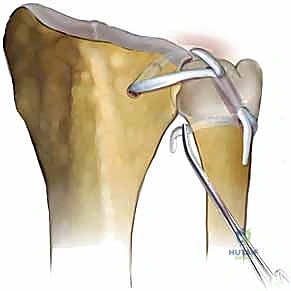

3. Bone Tunnel Placement

This is where we create the precise pathways for our graft, mimicking the native radioulnar ligaments.

- Radial Tunnel Preparation:

- Using careful subperiosteal dissection, elevate the soft tissue from the dorsal edge of the sigmoid notch for several millimeters. This exposes the bone for tunnel placement.

- Identify the appropriate starting point for the radial tunnel: it should begin several millimeters proximal to the lunate fossa and approximately 5 mm radial to the articular surface of the sigmoid notch. This placement is crucial to avoid violating the articular cartilage and to ensure isometric graft placement.

- The tunnel should be oriented parallel to the articular surfaces of both the sigmoid notch and the lunate fossa.

- Drive a guidewire for a 3.5-mm cannulated drill bit from dorsal to volar through the radius, aiming for the volar aspect of the radius, distal to the pronator quadratus insertion.

- Fluoroscopy is mandatory here, fellows. Obtain both AP and lateral views to confirm precise guidewire placement, ensuring it's not too close to the articular surface and is exiting in a safe volar location.

* Once confirmed, use the 3.5-mm cannulated drill bit to create the radial tunnel. Irrigate to cool the bone.

* Ulnar Tunnel Preparation:

* Elevate the ulnar flap of the DRUJ capsulotomy to expose the ulnar head and neck, again, being scrupulous not to injure the ECU tendon sheath.

* Now, we need to access the ulnar fovea. Flex the wrist and pronate the forearm to help retract the TFCC remnant and provide better visualization.

* The ulnar bone tunnel will travel from the ulnar fovea to exit on the lateral ulnar neck, just volar to the ECU tendon.

* Retrograde Technique (Preferred): Pass a guidewire retrograde from the ulnar fovea (identified by its characteristic depression) to exit on the lateral ulnar neck. Confirm this position with fluoroscopy.

* Antegrade Technique (Alternative): If exposure of the fovea is inadequate despite wrist flexion, you may create the tunnel antegrade from the lateral ulnar neck to the fovea. If using this approach, be extremely careful to protect any remaining TFCC tissue and the ulnar carpus with a blunt probe or elevator as the drill exits.

* Confirm guidewire position with fluoroscopy.

* Drill the ulnar tunnel. Remember, this tunnel must accommodate both limbs of the tendon graft, so you may need to enlarge it slightly with a standard drill bit after the initial 3.5mm cannulated drill.

4. Graft Passage

This is a multi-step process requiring careful coordination and visualization.

- Volar Exposure for Radial Tunnel Exit:

- Make a second exposure to visualize the volar aspect of the radial bone tunnel. This involves a 3-cm longitudinal incision extending proximally from the proximal wrist crease, slightly radial to the previous graft harvest incision.

- Carefully dissect down between the ulnar neurovascular bundle (ulnar artery and nerve) and the finger flexor tendons to reach the volar surface of the radius. Protect these vital structures meticulously.

* Passing Graft through Radius:

* From the dorsal wound, pass a suture passer (or a curved hemostat with a suture) through the radial bone tunnel from dorsal to volar.

* In the volar wound, grasp one end of your harvested tendon graft (which we've pre-sutured with a leading suture, of course) and pull it back through the distal radius tunnel from volar to dorsal.

* Intra-articular Passage:

* Now, in the dorsal wound, you'll have one end of the graft exiting the radial tunnel. Take the other end of the graft.

* From dorsal, pass a straight hemostat over the ulnar head, piercing the volar DRUJ capsule just distal to the ulnar head. Use a blunt technique to avoid neurovascular injury.

* Grasp the free end of the graft with the hemostat and pull it through this capsular opening into the ulnocarpal joint space.

* Both tendon ends should now be visible through the dorsal wound: one exiting the radial tunnel, and the other having passed through the volar capsule.

* Passing Graft through Ulna:

* Using a suture retriever or a curved hemostat, pass both tendon ends through the ulnar bone tunnel, starting from the fovea and exiting at the ulnar neck.

* Wrapping the Graft:

* This is the final anatomical configuration. A curved hemostat is used to guide the two tendon ends around a portion of the ulnar neck in opposite directions.

* One limb of the graft should pass deep to the ECU sheath, reconstructing the dorsal radioulnar ligament.

* The other limb should pass around the volar neck of the ulna, reconstructing the volar radioulnar ligament.